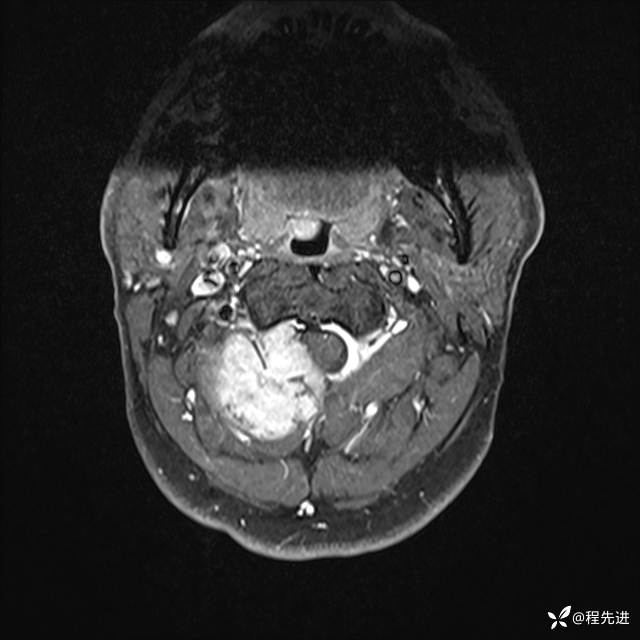

MRI平扫+增强:

T1增强: